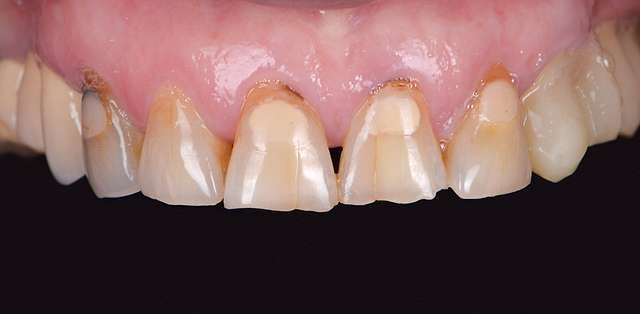

As time goes by, teeth start to wear physiologically, and become shorter. Their proportions start to change and this is perceived as an aging effect. Central dominance is lost, which is one of the main characteristics of a young smile. Gums start to recede and black triangles form in their absence.

And off course the various treatments leave their mark as they reach their lifetime. All of these can be rehabilitated via redesign using ceramic veneers and crowns. Rejuvenation happens as the youthful features are re-embedded in design. Smile rejuvenation is a major component of facial rejuvenation.